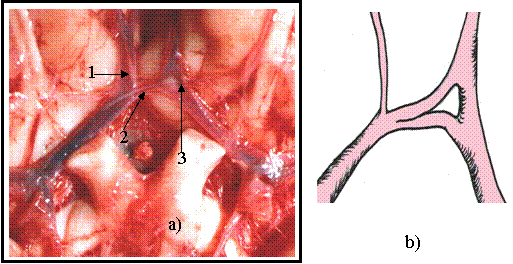

Cazul - 1- [ figura nr. 9.1 a) si b).]

Figura 9.1 Artera comunicanta anterioara

a) - artera comunicanta anterioanta accesorie

b) b) - prezentare schematica

La acest caz este semnalata o artera comunicanta anterioara accesorie cu diametrul de 0,5mm., lungime de 5mm. Un vas cu diametrul sub 1mm. in literatura este considerat nefunctional totusi de la aceasta comunicanta emerg vase pentru fata superioara a chiasmei optice.